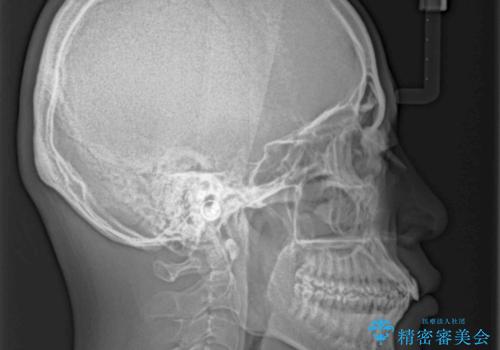

患者様と相談の上、横顔の印象から抜歯矯正は必要ないと判断し、IPR(歯と歯の間)並びに歯列全体の後方移動により口元の突出感の改善することとしました。

しっかりと装着時間を守り、ゴムかけも徹底していただいたので、思いの外口元を引っ込めることができました。

これ以上の改善を望まれましたが、非抜歯矯正でこれ以上口元を引っ込めると食いしばりすやすい咬合となるため、この歯列で終了としました。